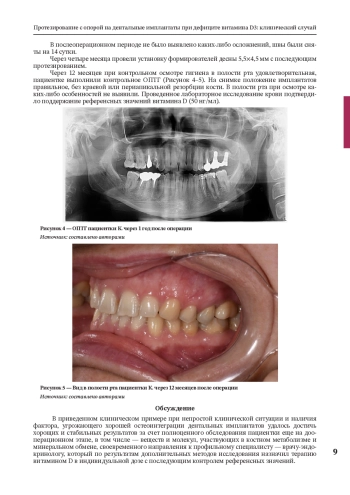

Регулирование витамином D метаболизма фосфата кальция и ремоделирования костей, а также противовоспалительные и иммуномодулирующие эффекты, регуляция пролиферации и дифференцировки клеток могут существенно повлиять на здоровье полости рта. Ряд клинических исследований и научных экспериментов продемонстрировал связь между низким уровнем витамина D и течением, и частотой рецидивирующего афтозного стоматита, ответом на лечение плоскоклеточного рака полости рта, тяжестью заболеваний пародонта, процессами остеоинтеграции и ремоделирования кости после дентальной имплантации и направленной костной регенерации. В данной статье мы приводим описание клинического случая протезирования с опорой на дентальные имплантаты у пациентки при выявленном дефиците витамина D3. Одним из основных этапов лечения являлось предоперационное обследование, включавшее оценку гормонального статуса и минерального обмена, в том числе — витамина D, паратгормона и маркеров остеогенеза, совместную работу с врачом-эндокринологом, назначение индивидуальной дозы витамина D для достижения референсных значений в сыворотке крови и дальнейшей поддерживающей дозы, что позволило достичь хорошей остеоинтеграции дентальных имплантатов и провести своевременное протезирование пациентки.